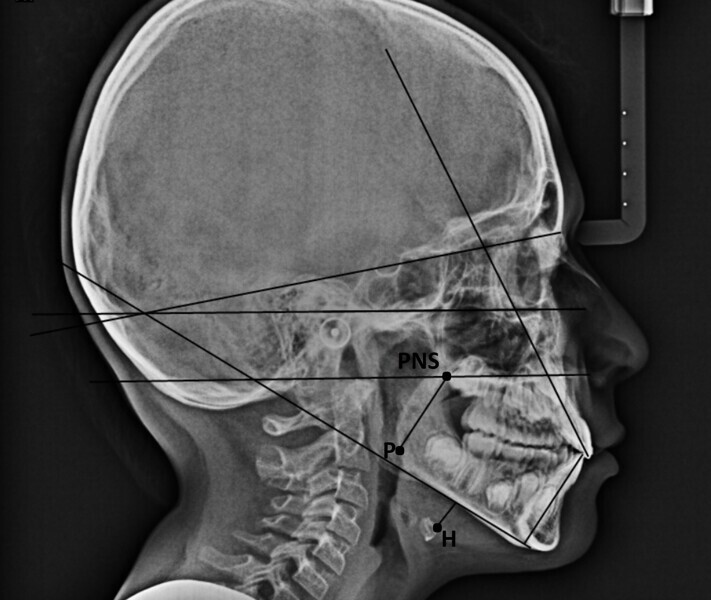

In my clinical practice, I prevent patients from rolling and rotating their heads using a cephalostat while allowing pitching: only after they have positioned themselves comfortably, do I place the post on the nasion, without exerting pressure. In this way, the patient will assume his or her habitual posture, and this too will be investigated by us. The cephalometric radiograph showed very important dysfunctional aspects (Fig. 4). Antero-rotation of the head and cervical hyper-lordosis were evident. Tracing of the tongue23 showed a very low position of the anterior part, as was found clinically. Cephalometric analysis was performed using the OrisCeph Rx1 CE program (Version 7.70; Elite Computer Italia). The patient showed a Class I skeletal pattern with antero-rotation of the maxillary plane, proclination of the mandibular incisors and increased anterior lower face height.

In the control cephalometric radiograph, the lingual position had completely regularised, the body and tip being in contact with the hard palate, creating an average overbite (Fig. 14). The cervical hyper-lordosis was moving towards correction and the skull posture was less forward.

Functional cephalometric analysis showed clear improvements too (Fig. 15; Table 1). The maxillary plane, which indicates the orientation of the maxilla, had undergone regularisation in both the angle with the skull base (SN line; going from a value of 7.7° at T0 to one of 11.2° at T1) and the angle with the Frankfort plane (going from a value of −2.9° at T0 to one of 0° at T1). The inter-incisal angle had increased, indicating an improvement in the inter-incisal ratios. The excessively divergent angle between the maxillary plane and the mandibular plane had decreased, and the facial divergence regarding both the mandibular angle and the face height index showed remarkable normalisation. Of note, was the reduction in proclination of the mandibular incisors, which went from a mandibular incisor to mandibular plane angle of 96.8° to one of 92.1°.

In agreement with Yoon et al.,4 in the radiographs at T0 and T1, we also calculated the length of the soft palate because its increase in size, as far as we know, is considered a risk factor for the development of obstructive sleep apnoea, and its reduction is part of the therapeutic goals of myofunctional therapy for the treatment of obstructive sleep apnoea.28, 29 The P–PNS value had decreased from T0 (30.0 mm) to T1 (29.4 mm). Also in agreement with Yoon et al.,4 we also calculated the length of the perpendicular from the hyoid bone to the mandibular plane. An increase indicates a low tongue posture. This line had fallen from T0 (16.3 mm) to T1 (11.9 mm), giving further confirmation of improved lingual posture.